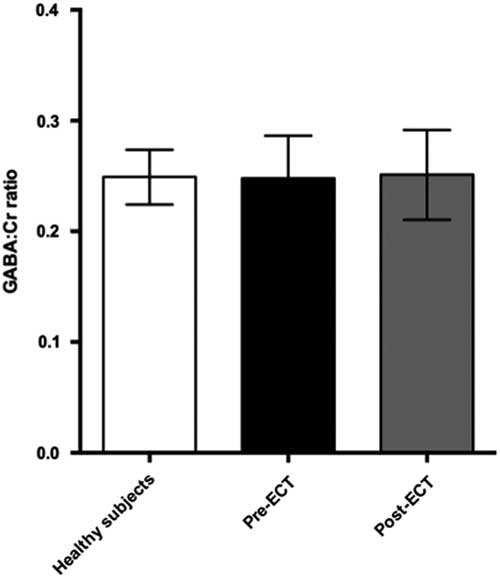

GABA measurements in PFC

Fig. 4 Plot of GABA:Cr ratios in prefrontal cortex showing mean ± SD. ECT, electroconvulsive therapy; GABA, γ-aminobutyric acid.

Comparing pre- and post-ECT GABA/Cr levels, we found no significant changes (t=0.10, p=0.92) as the mean GABA/Cr ratio was 0.249 (±0.04) pre-ECT, and 0.251 (±0.04) post-ECT. There was no correlation between changes in HAM-D17 rating scores and the fractional GABA/Cr changes [(GABApost−GABApre)/GABApre] (r(8)=0.43, p=0.21). Moreover, no significant correlation was found between pre- or post-ECT GABA/Cr levels and HAM-D17 ratings (p=0.77 and p=0.236, respectively).